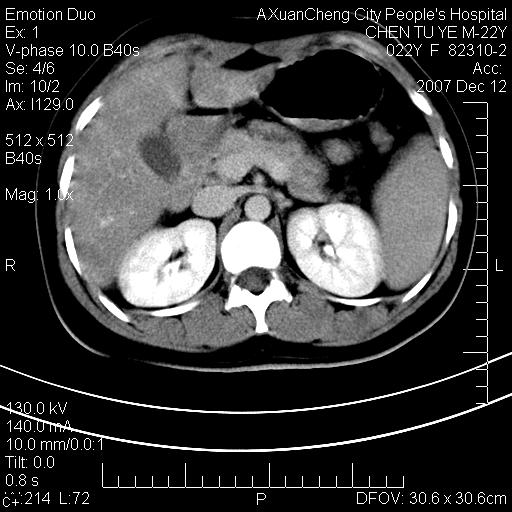

超声提示肝右前叶占位,约2.5cm.

各位战友看看病灶在什么地方,可是右前叶进肝裂部低密度影,平扫ct值约10以下,增强后增高明显

1 脾大,慢性肝损伤. 2 肝脏脂肪侵润.  3 你所指的部位疑点,我没看出有问题.

脂肪肝.楼主所指部位不考虑异常,为肝圆韧带影.

脂肪肝,脾大

平扫与增强ct值差>10hu的话,应该列为高度疑似病例,我们的职责就是不能放过这样小的病灶.再次b超对比

确定是否同一病灶!运到伪影我坚决反对!